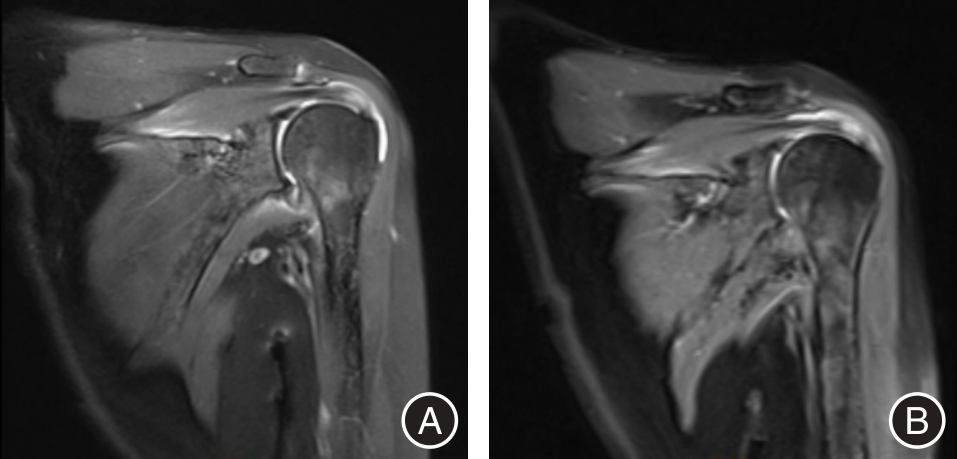

目的 探讨上肢康复机器人(ULRR)联合超声定位体外冲击波(ESW)在轻、中度肩袖损伤治疗中的应用效果。 方法 选取2023年1月至2024年3月安徽医科大学第二附属医院收治的90例轻、中度肩袖损伤患者,随机分A组(基础康复)、B组(基础康复+ESW)、C组(基础康复 + ESW + ULRR)各30例。于治疗前后采用视觉模拟评分(VAS)评估患者肩部疼痛,肩关节位置重现偏差角度评估患者本体感觉,表面肌电图(sEMG)检测患肩三角肌中束、冈上肌、冈下肌积分肌电值(iEMG)和均方根值(RMS),标准量角器测量患肩外旋、外展和前屈主动活动范围(AROM),Constant-Murley肩关节评分(CMS)评估患者肩部整体功能,评估对比3组疗效及满意度。 结果 治疗后,3组患者VAS评分和肩关节位置重现偏差角度显著下降,三角肌中束、冈上肌、冈下肌iEMG和RMS,肩外旋、外展和前屈AROM,以及CMS各项评分(疼痛、日常生活活动、主动活动范围、肌力)显著升高,且C组以上各项指标改善均明显优于A组和B组,差异均有统计学意义(P < 0.05);C组临床有效率和患者满意度明显高于A组和B组,差异均有统计学意义(P < 0.05)。 结论 对轻、中度肩袖损伤患者,上肢康复机器人联合体外冲击波具有更好的治疗效果,能缓解疼痛,还能改善运动功能和本体感觉,提高患者满意度。

Objective To investigate the therapeutic efficacy of the combination of upper limb rehabilitation robots (ULRR) and ultrasound-guided extracorporeal shock wave (ESW) in the treatment of mild to moderate rotator cuff injuries. Methods A total of 90 patients with mild to moderate rotator cuff injuries, who were admitted to the Second Affiliated Hospital of Anhui Medical University between January 2023 and March 2024, were selected and randomly assigned to three groups: Group A (basic rehabilitation), Group B (basic rehabilitation + ESW), and Group C (basic rehabilitation + ESW + ULRR), with 30 patients in each group. Before and after treatment, shoulder pain was assessed using the visual analogue scale (VAS). Proprioception was evaluated based on shoulder joint position reproduction error. The integral electromyography (iEMG) and root mean square (RMS) values of the median tract, supraspinatus, infraspinatus, and deltoid muscles on the affected side were measured using surface electromyography (sEMG). The active range of motion (AROM) for external rotation, abduction, and forward flexion of the affected shoulder was measured using a standard goniometer. Overall shoulder function was evaluated using the Constant-Murley Shoulder Score (CMS). The clinical efficacy rate and patient satisfaction levels were compared among the three groups. Results After treatment, the VAS score and shoulder position reproduction deviation angle in all three groups significantly decreased. Additionally, the iEMG and RMS values of the middle deltoid, supraspinatus, and infraspinatus muscles; the AROM of shoulder external rotation, abduction, and forward flexion; and the CMS scores (including pain, activities of daily living, active range of motion, and muscle strength) all showed significant improvement. Furthermore, the degree of improvement in all evaluated parameters in Group C was significantly greater than that observed in Groups A and B (P < 0.05). Moreover, Group C demonstrated a significantly higher clinical response rate and greater patient satisfaction compared to Groups A and B (P < 0.05). Conclusion For patients with mild to moderate rotator cuff injuries, the integration of an upper limb rehabilitation robot with extracorporeal shock wave therapy demonstrates superior therapeutic outcomes, effectively alleviating pain, enhancing motor function and proprioception, and increasing overall patient satisfaction.